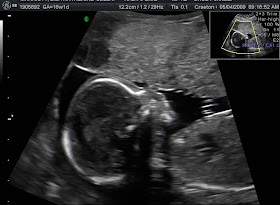

First And Second Trimester So Far Baby 2

www.pbfingers.com